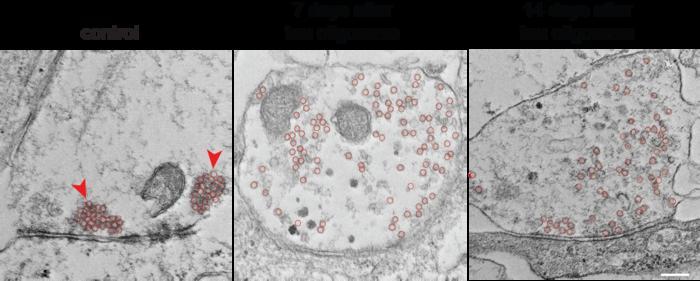

Electron microscopy images of human neuron synapses 7 or 14 days after a 30-minute exposure to tau oligomers or vehicle control. In vehicle-treated neurons synaptic vesicles (red circles) are clustered near the active zone (red arrows), whereas tau oligomer-treated neurons show increased vesicle number with reduced clustering and a more dispersed vesicle distribution. Scale bar: 200 nm. Magnification: 50,000x